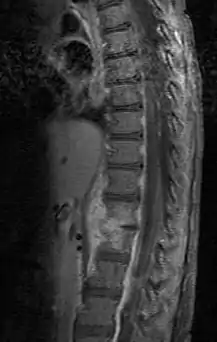

![]() Дисцит з паравертебральним абсцесом у дворічної дитини, сагітальне МРТ-зображення Дисцит з паравертебральним абсцесом у дворічної дитини, сагітальне МРТ-зображення | |

Лабораторні дані можуть свідчити про запальний процес (лейкоцитоз, підвищення рівня CRP та інших маркерів запалення), але також іноді можуть залишастись не зміненими. На рентгенівському зображенні тканина міжхребцевого диска на пізніх стадіях здається здавленою, а на початкових часто відсутні патологічні ознаки. Магнітно-резонансна томографія з контрастною речовиною є мотодом вибору діагностики спондилодисциту, а в деяких випадках також і комп'ютерна томографія. Наявність збудника може бути підтверджена через гемокультуру (посів крові), і пункційну біопсію міжхребцевого диска.